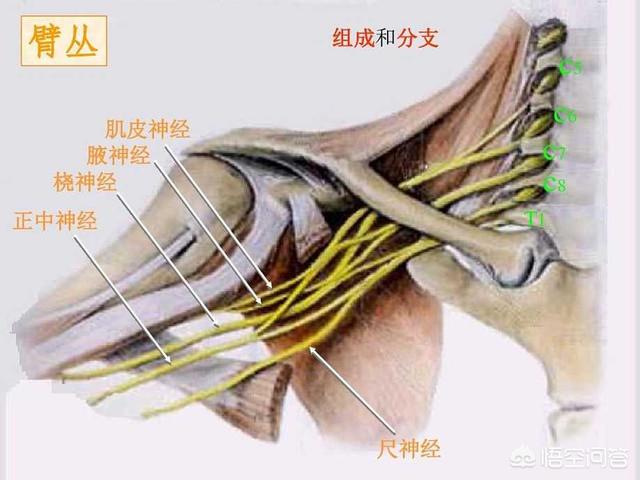

指の知覚神経は頸髄から神経根に分かれ、頸部腋窩で腕神経叢を形成し、上腕と前腕を通って橈骨神経、正中神経、尺骨神経となり、手と指に分布する末梢神経となる。

頚髄神経根を分割し、頸部に形成する。腕神経叢分ける橈骨神経、正中神経、尺骨神経経絡は上腕と前腕を等距離に通過し、最終的に頚椎となる。末梢神経手と指に分布している。そのため、指先のしびれは必ず上記の神経に問題がある。

2.橈骨神経、正中神経、尺骨神経の損傷

上腕外側面の中央下部にある橈骨神経は、次のような影響を受ける。圧迫、外傷、腫瘍などにつながる可能性がある。親指と人差し指の裏側のしびれと痛み、指と手首の下垂。.正中神経が損傷すると、次のようなことが起こる。手のひら、親指、人差し指、中指のしびれと痛み。尺骨神経の損傷はその結果である。尺骨神経の損傷は、その後、次のような結果をもたらす。同側の小指と薬指にしびれと痛みがあり、一部の指の動きが悪くなる。